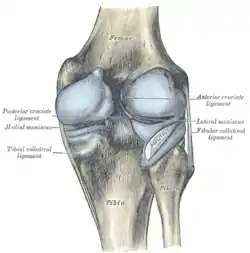

Anatomy

Skeletal components involved in the unhappy triad include: patella, femur, tibia. No muscles are directly involved in this injury, only ligaments; However, strengthening the hip flexor and hip extensor muscles may help alleviate the injury.

The medial collateral ligament, posterior cruciate ligament, anterior cruciate ligament, and lateral collateral ligament are the four primary ligaments of the knee. The medial and lateral collateral ligaments primarily provide support to varus and valgus forces whereas the anterior and posterior cruciate ligaments prevent anterior and posterior translation of the tibia on the femur.[2]

Structures in triad

The classic O'Donoghue triad is characterized by an injury to three knee structures (in order):

- the anterior cruciate ligament

- the medial meniscus (however, lateral meniscus[1] injuries are more commonly seen among athletes, leading to the definition of the O'Donoghue triad most commonly used today.) [3][4][5]

- the medial collateral ligament (or "tibial collateral ligament")